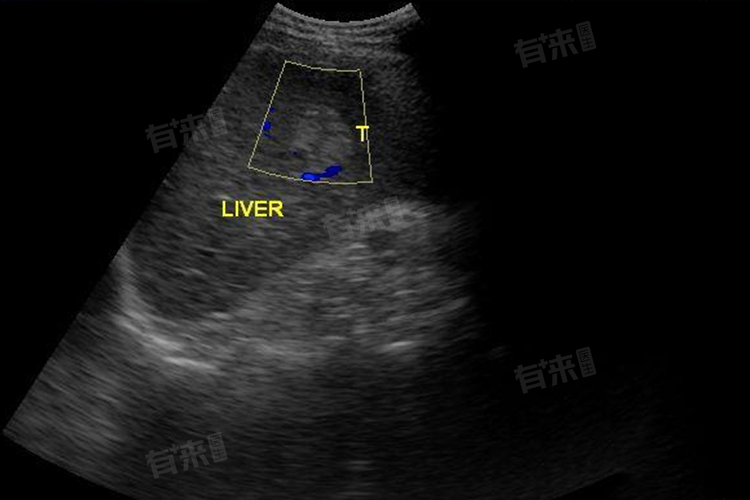

肝内高回声是否需要治疗,需要根据具体情况来判断。一般来说,肝内高回声可能意味着肝脏组织存在某种异常,这种异常可能是良性的,也可能是恶性的,需要进一步的检查来确定其性质。

- 如果肝内高回声是由良性病变引起的,如肝血管瘤、肝内胆管结石、胆囊结石等,虽然这些病变通常不会对患者的生命造成直接威胁,但可能会引发一些不适症状,如腹痛、恶心、呕吐等。即使是良性病变,也存在恶变的可能性,尤其是在长期未得到有效治疗的情况下。对于良性病变引起的肝内高回声,虽然不一定需要立即治疗,但应定期进行超声检查,必要时完善增强CT或增强核磁检查,明确病变的变化情况,并在医生的指导下进行必要的随访和干预。

- 但如果肝内高回声是由恶性病变引起的,如原发性肝细胞癌、肝脏转移瘤等,那么治疗就显得尤为重要。这些恶性病变会对患者的生命安全构成严重威胁,需要及时进行手术切除、化疗、放疗等综合治疗手段,以防止病情进一步恶化。

肝内高回声的出现还可能与其他因素有关,如脂肪肝、酒精性肝病、乙型病毒性肝炎等肝脏疾病。这些疾病也会对肝脏造成不同程度的损伤,影响肝脏的正常功能。对于肝内高回声的患者,还需要关注肝脏的健康状况,积极治疗肝脏疾病,以维护肝脏的正常功能。但无论如何,定期进行超声检查、关注肝脏健康状况、积极治疗肝脏疾病都是非常重要的。